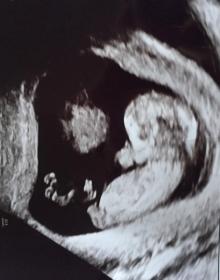

Any guesses?![]()

Thread: 12+4 weeks nub theory??

12+4 weeks nub theory??

Boy!

Maybe boy but I'm not entirely sure that's the nub. The pics are kinda small.